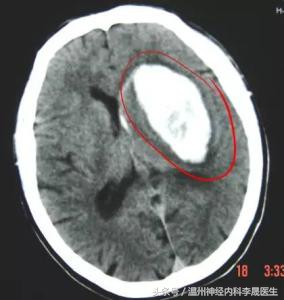

2.脑叶出血

常由脑AVM、Moyamoya病、脑淀粉样血管病、肿瘤卒中等所致,占5~10%

以顶叶最常见,其次为颞叶、枕叶、额叶,可有多发脑叶出血。 临床可表现为头痛呕吐,癫痫发作较多,肢体瘫痪较轻,昏迷少;根据累及脑叶的不同,出现局灶性定位症状和体征。

①年轻人多见于血管畸形,Moyamoya病,血肿边不规则,血肿内混杂密度。

②老年人多见于脑A硬化,类淀粉样血管病,肿瘤等。

2 颞叶—瘫痪、面舌瘫、上象限盲,幻视幻嗅,精神症状,颞叶癫痫,感觉性失语(优势半球)等。

(A)左侧颞叶大出血压迫同侧侧脑室;(2)较小的右侧颞叶出血